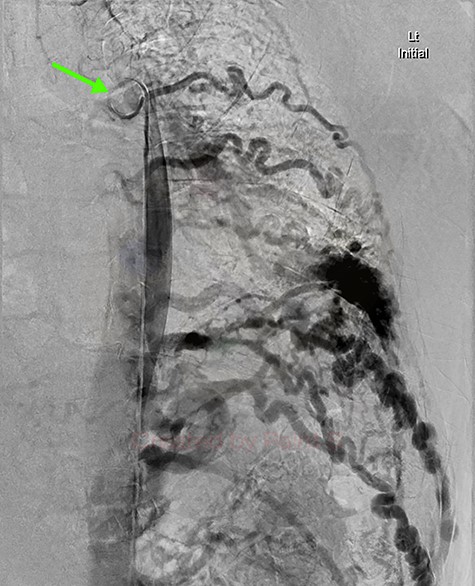

DSA utilizing superselective catheterization to demonstrate contribution to the PAVM via one of the many tortuous intercostal arteries.

Given the findings, he was referred to Interventional Radiology for a formal digital subtraction angiogram with view of transcatheter embolization. Under local anaesthetic and sedation, a 5-french sheath was placed in the left common femoral artery. Using a 5-french pigtail catheter, aortic angiography was undertaken, confirming the CTPA findings and demonstrating predominant supply of the vascular malformation via the left intercostal arteries and the left inferior phrenic artery (Fig. 4)—draining into the left inferior pulmonary artery and vein. Superselective catheterization of the left intercostal arteries (Fig. 5) and the left inferior phrenic artery (Fig. 6) are shown. Unfortunately, due to the malformation’s volume and complexity, embolization was abandoned. He was subsequently referred to Cardiothoracic Surgery, currently awaiting consideration and workup for ligation and resection via video-assisted thoracoscopy, and potentially thoracotomy.